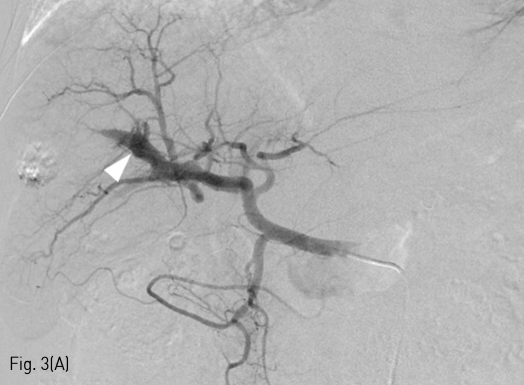

Fig 3A

Embolization of massive arterioportal shunt. The common hepatic arteriography (A) and S7 segmental hepatic arteriography (B) showed massive arterioportal shunt (arrowhead) between a branch of the S7 segmental hepatic artery and right posterior portal vein. A connection (arrow) between the S7 segmental hepatic artery and right posterior portal vein was identified on arteriography.

5Fr RH catheter (Cook, IN, USA)를 이용하여 총간동맥을 선택한 후 시행한 선택적 조영술에서 우측 후방 간문맥이 조영되면서 7번 간분절 동맥과 문맥 사이의 대량의 간동문맥단락 소견이 있었다(Fig. 3A, 3B). 1.9Fr microcatheter (Radiostar, Taewoong, Gyeonggi-do, Korea) 를 이용하여 간동문맥단락의 원인이 되는 혈관을 superselection 한 후, Interlock detachable coil (Boston scientific, MA, USA) 2mmx6cm과 K3 pushable coil (Taewoong, Gyeonggi-do, Korea) 2mmx2cm, 2mmx5cm을 이용하여 코일 색전술을 시행하였다 (Fig. 3C). 추가로 N-butyl-2-cyanoacrylate (histoacryl; B.Braun)와 Lipiodol (Guerbet) 1:3 혼합물 0.5mL을 이용하여 색전술을 시행하였다 (Fig. 3D). 색전술 후 시행한 간동맥의 선택적 조영술에서 간동문맥단락이 소실됨을 확인하였다(Fig. 3E).